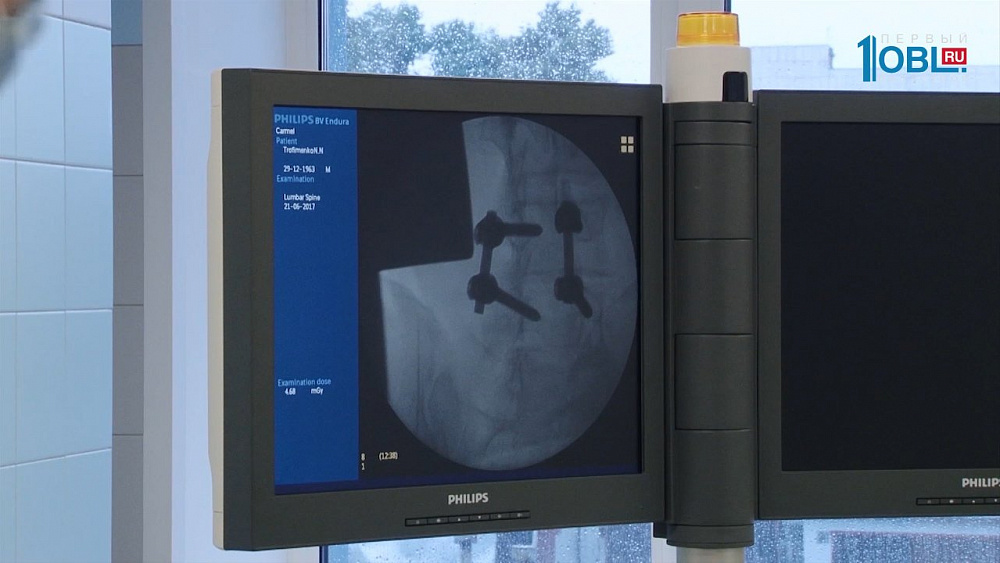

Боль в пояснице — одна их самых частых жалоб пациентов самого разного возраста. Даже во время лечебных осмотров в школах ежегодно выявляют сколиозы — боковые искривления позвоночника, которые неминуемо приводят к раннему появлению грыж межпозвоночных дисков. Почему появляется боль в спине и что делать, если она уже появилась?